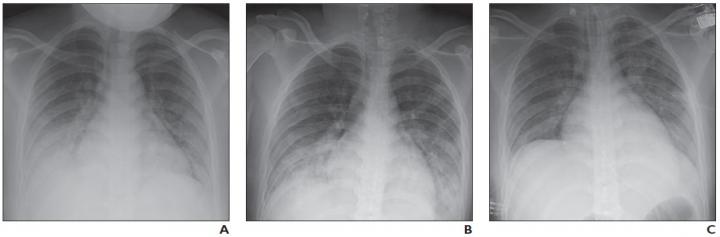

A, Frontal chest radiograph obtained at initial presentation shows bilateral lower lung zone-predominant consolidations and, to lesser extent, ground-glass opacities. B, Frontal chest radiograph obtained 2 days after hospital admission shows interval increase in consolidation in bilateral lower lung zones. C, Frontal chest radiograph obtained 6 days after hospital admission and treatment shows interval improvement in consolidations in bilateral lower lung zones.

At most institutions, whereas the first imaging study performed in patients with clinically suspected COVID-19 is chest radiography, Foust and colleagues' review of the clinical literature found that studies on chest radiography findings in patients with COVID-19 were relatively scarce.

Regarding the limited studies of pediatric patients with COVID-19, Foust et al. noted chest radiography "may show normal findings; patchy bilateral ground-glass opacity (GGO), consolidation, or both; peripheral and lower lung zone predominance."